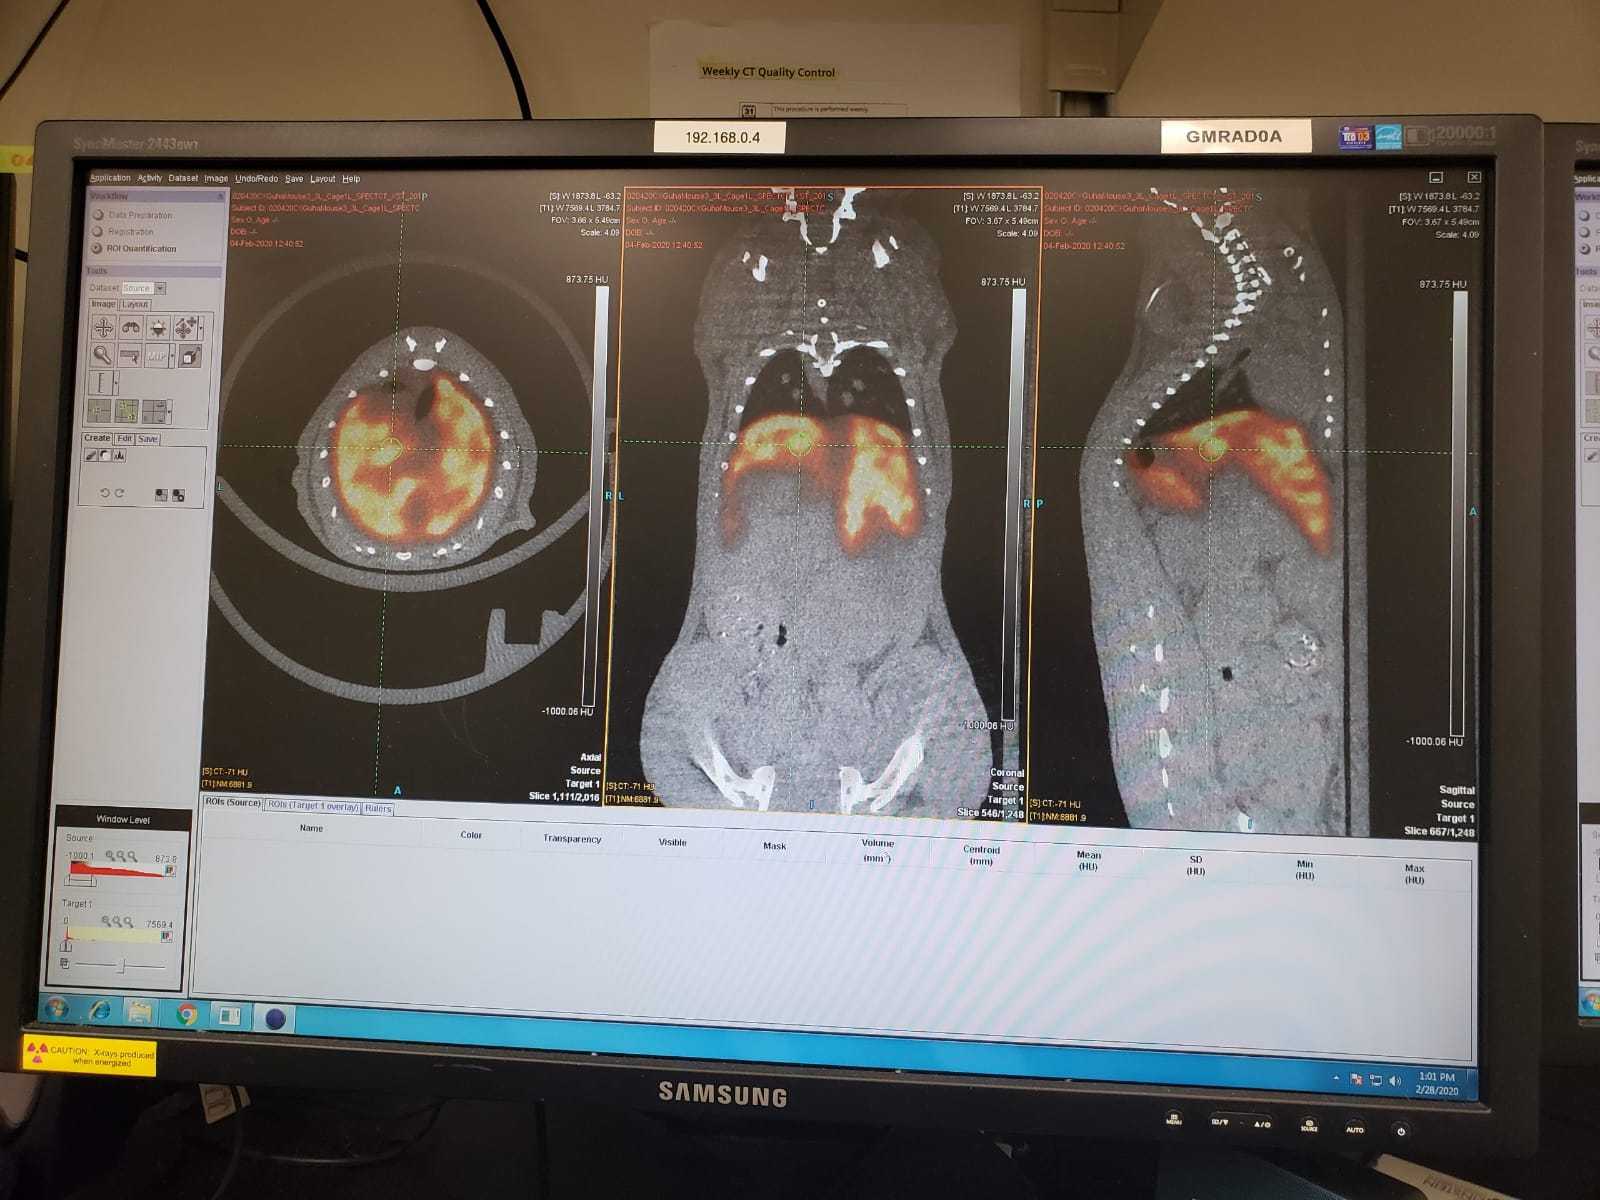

A pioneering program in its category, Montefiore Einstein’s Nuclear Medicine Residency Program is nationally and internationally recognized for its leading research in developing radioimmunotherapies. We offer a rich educational experience in which our trainees learn to manage a diverse array of clinical presentations using a wide range of diagnostic and therapeutic procedures.

Moses Campus, along with Children’s Hospital at Montefiore Einstein, features 726 adult inpatient beds and 106 pediatric inpatient beds. The facility also offers services to outpatients. As an NCI-Designated Cancer Center, Moses provides diagnostic and therapeutic modalities through an active theranostics program. While training at Moses, residents partake in a particularly rigorous program in oncologic and non-oncologic pediatric and adult nuclear medicine. Our Transplant Center, also on-site, affords residents the ability to evaluate organ physiology pre- and post-transplant.